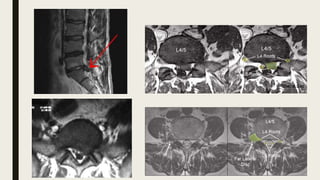

L4-5 central disc extrusion

Investigation - FilmL-S spine Lateral